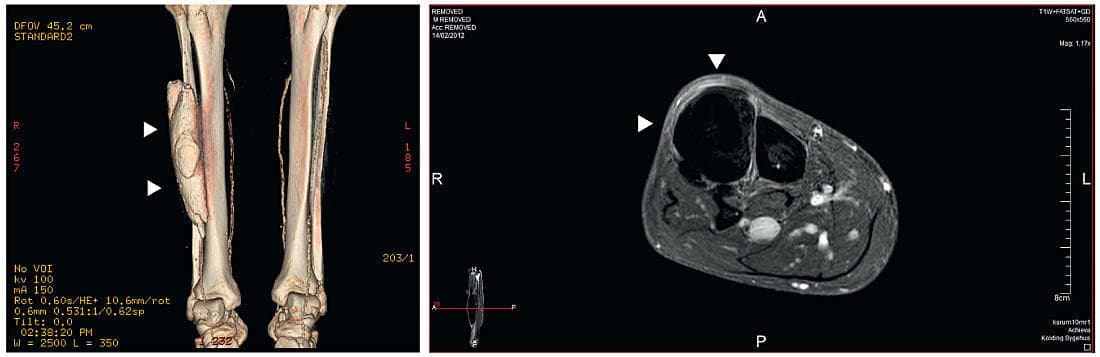

Der blev foretaget ultralydskanning af crus på mistanke om absces. Svaret viste overraskende en central kalcifikation uden kontakt til den underliggende knogle. Der blev foretaget røntgenundersøgelse, magnetisk resonans-skanning og computertomografi af crus for at udelukke malignitet. Disse undersøgelser viste en kalcifikation i peroneuslogen.

Patienten havde således en heterotopisk ossifikation af peroneuslogen, som blev fundet tilfældigt [1-3], samtidig med at der var klinisk mistanke om erysipelas. Patienten blev behandlet med penicillin, og efter fem dage var symptomerne svundet, men den hårde udfyldning bestod.